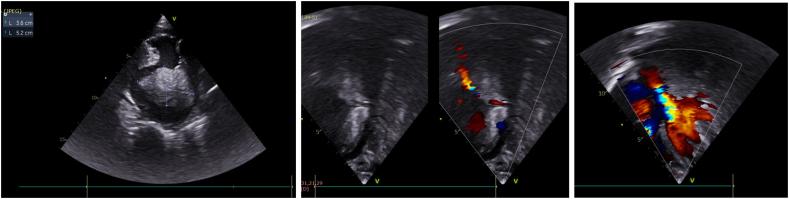

An 11-year-old girl presented at an emergency department with two months of progressive dyspnea with malnutrition. A fused mass was found in LA on an echocardiogram along with moderate MR, severe MS, and mild pericardial effusion. CT scan showed a massive pleural effusion with a solid mass in the left lung obstructing the left bronchial tree, accompanied by the expansion of the tumor mass into the left pulmonary vein and LA.

一名11岁女童因进行性呼吸困难2个月伴营养不良就诊于急诊科。超声心动图显示左心房有一个融合性肿块,伴有中度二尖瓣反流、重度二尖瓣狭窄和轻度心包积液。CT扫描显示大量胸腔积液,左肺有一个实性肿块阻塞左支气管树,同时肿瘤肿块延伸至左肺静脉和左心房。